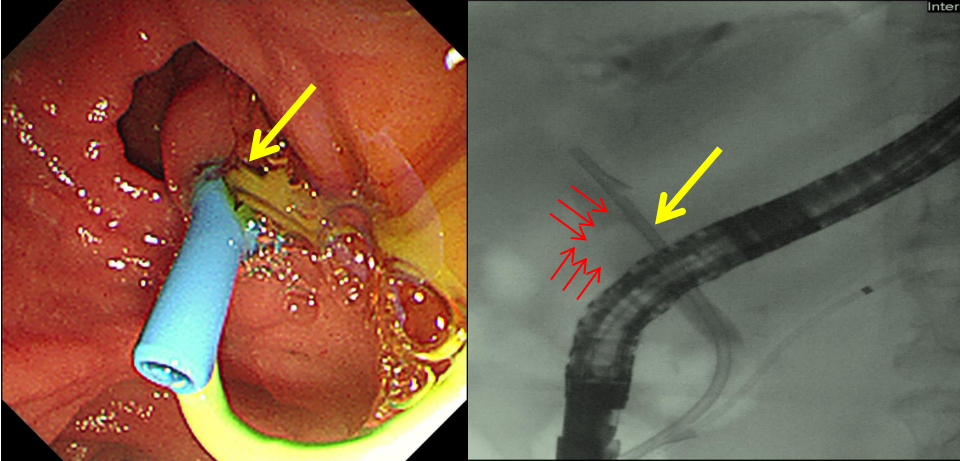

为保障手术安全,麻醉科王俊副主任会诊评估、奚曼医生实施静脉复合麻醉,ERCP治疗组长矫太伟副教授为病人快速实施ERCP手术。术中造影明确胆总管结石嵌顿于肝总管,堵塞胆道通路。团队精准操作,考虑患者心衰,胆系感染,化脓性胆管炎,一般状态差,无法耐受长时间胆管取石操作,故先快速微创置入胆道支架解除胆道梗阻,引出大量脓性胆汁降低胆道压力。支架置入后,患者腹痛、发热等急性胆管炎症状迅速缓解,感染得到有效控制。

左图箭头所指为支架置入后脓性胆汁涌出,右图黄色箭头所指为胆管塑料支架、红色箭头所指为胆总管结石